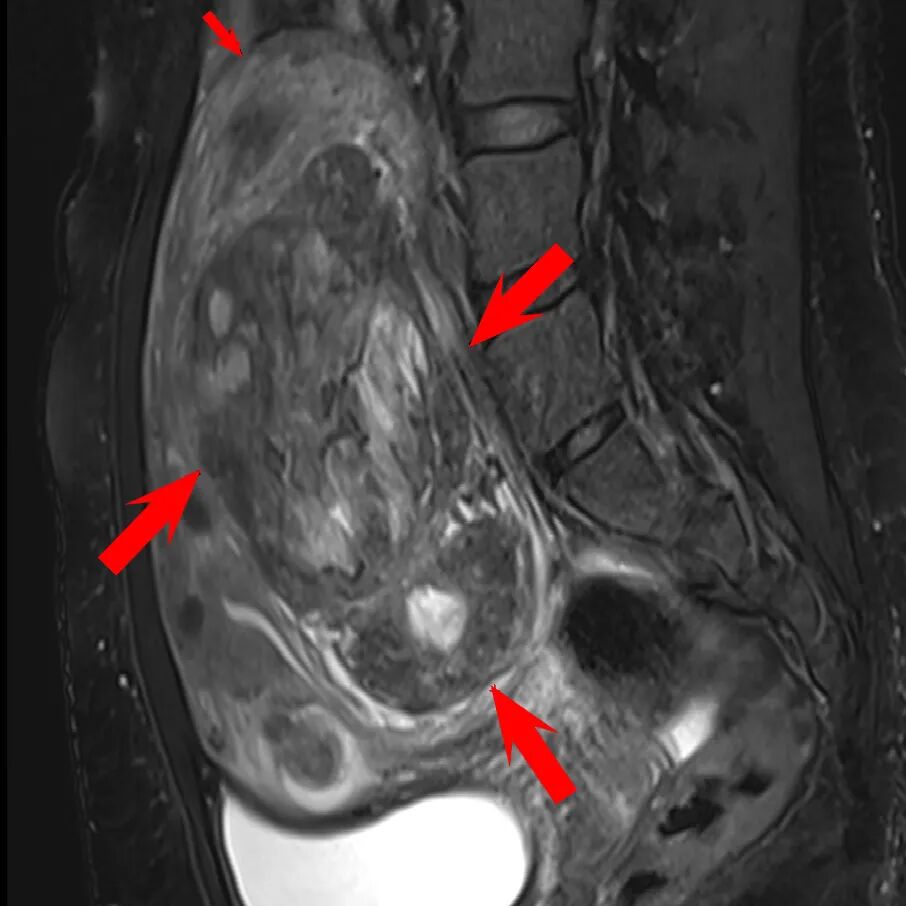

45岁的陈女士在一次输尿管结石诊治过程中,被发现患有巨大子宫肌瘤,腹部膨隆如怀孕5个月。更棘手的是,患者有1型糖尿病10余年,每天预混胰岛素用量达60单位,血糖控制仍欠佳,餐后血糖时达11-12mmol/l左右。

▲患者磁共振影像

此前,陈女士曾辗转多地求诊,得到的建议多为开腹手术。但对于糖尿病患者而言,较大的手术切口意味着更高的感染风险,也更容易出现脂肪液化、切口愈合不良等问题。这让她对手术顾虑重重,焦虑明显。